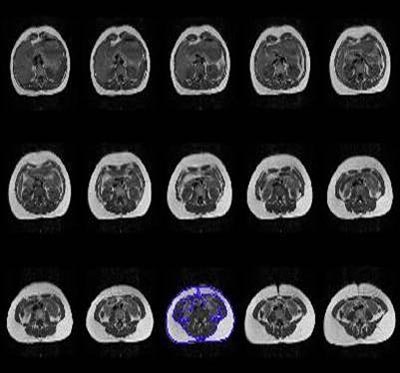

![]() |

| Above, multiple abdominal MR images from a single subject demonstrate the entire volume of the abdomen. The color is on the image used to calculate the single slice data. Images courtesy of Dr. Lane Donnelly. |